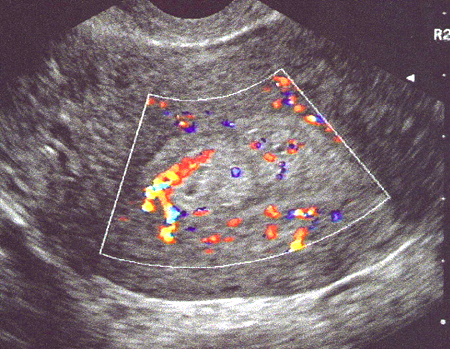

Polype muqueux, hyperéchogène avec pédicule vasculaire au Doppler couleur.

Coupe transversale (Cliché : Dr. C. TALMANT

)